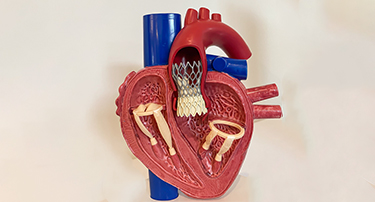

Modern Cardiac Care: The Role of TAVR in Structural Heart Disease Treatment

Nature is just amazing. Look at the amazing things. Just look around, or better yet, look within yourself. Your heart, for example, is a true marvel, working tirelessly, 24/7, never taking even a nap.

TAVI Vs. Open-Heart Surgery: Which Is The Right Choice For You?

For heart valve replacement, patients usually have two primary choices: Transcatheter Aortic Valve Implantation (TAVI) and open-heart surgery. Both involve replacing a faulty aortic valve, but they are very different in approach, recovery period, and applicability to various patient populations. Knowing the main differences, advantages, disadvantages, and success rates can assist you in making an informed choice.